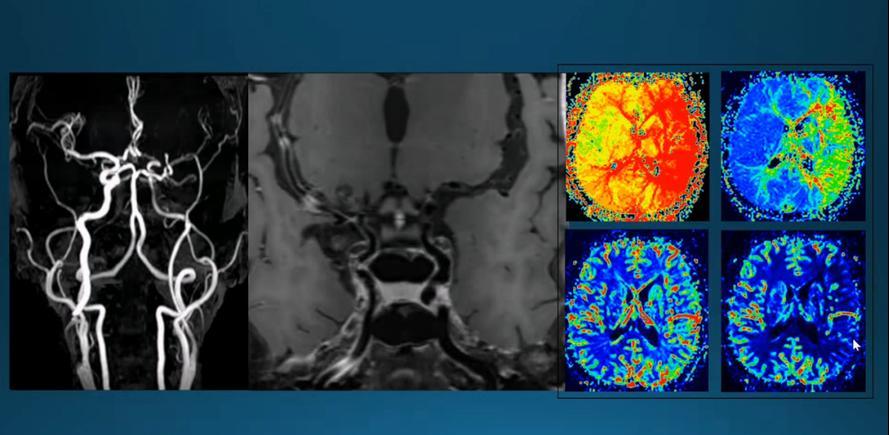

很多人在体检时,看着报告上那一堆项目,根本不知道哪个是关键的。有人一看到“脑供血不足”就慌了,立刻联想到中风;有人盯着血脂稍高的一栏,吓自己一整天;还有人看到“脑部白质稀疏灶”,就开始上网查,越查越害怕,最后走入“过度检查”的死循环。 但真正判断脑梗风险的,核心就两件事:脑血管成像检查,以及颈动脉超声。 别的,真可以先放一放。 脑血管成像能直观看出脑部大血管有没有狭窄、闭塞、畸形或者其他异常。它像是给整个脑血管系统拍了一张清晰的“路线图”,有没有哪段“路”堵了,看得一清二楚。

而颈动脉超声呢,是查输送血液到脑部的“主干道”——颈动脉有没有斑块、狭窄或血流异常。因为很多脑梗,其实是从颈动脉这口“大水管”堵起的。堵在入口,脑子自然供血受限。 结果呢?很多人被一些看似“高科技”的项目吸引,比如脑电图、基因筛查、认知功能评估,甚至一些含糊不清的“脑部能量分析”。但问题是,这些检查并不直接告诉你血管有没有堵住,也帮不了你预防或判断脑梗的风险。 有人会说,那我做个核磁共振不是更高级?但问题来了,核磁是看脑组织有没有损伤,不是看血管堵没堵。它可以看到过去有没有发生过小梗塞,但对“未来会不会梗”并不敏感。就像你想知道这条路会不会堵车,结果人家给你看的是上个月的路况照片。

这也是为什么,有些人明明核磁一切正常,转头就中风了。检查是方向错了。 而颈动脉超声,操作简单、无创、费用不高,信息量却极大。很多动脉粥样硬化、早期斑块、甚至血流速度异常,都能一眼看出。 但偏偏,它不够“炫”,也不够“高科技”,很多人觉得不值得做,反而花大钱去查一些根本没关联的项目。 说到底,脑梗不是神秘莫测的病,它有迹可循,有办法发现,也有机会提前干预。但前提是,你得走对方向。